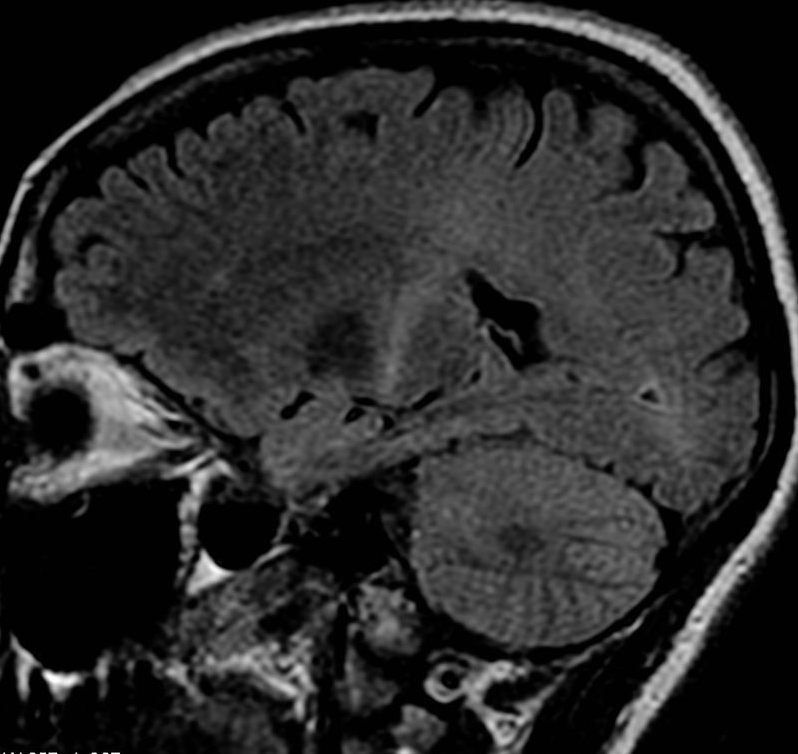

ONTT cũng phát hiện ra rằng trong số 389 bệnh nhân không được chẩn đoán mắc MS xác định hoặc có thể xảy ra trên lâm sàng khi bắt đầu nghiên cứu, nhóm dùng steroid tiêm tĩnh mạch cho thấy tỷ lệ phát triển MS xác định trên lâm sàng thấp hơn trong vòng 2 năm đầu (7,5%) so với nhóm dùng giả dược ( nhóm 16,7%) hoặc nhóm prednisone (14,7%). Hầu hết tác dụng có lợi này được thể hiện ở những bệnh nhân có kết quả chụp cộng hưởng từ (MRI) ban đầu bất thường gợi ý tổn thương mất myelin nhưng tác dụng bảo vệ rõ ràng này không được duy trì sau 3 năm. Các kết quả MRI ban đầu bất thường cho thấy 1 hoặc nhiều tổn thương mất myelin điển hình được chứng minh là yếu tố tiên đoán mạnh nhất cho sự phát triển của MS lâm sàng trong 15 năm tiếp theo (nguy cơ khoảng 72%). Trong số những bệnh nhân viêm dây thần kinh thị giác có kết quả MRI não cơ bản bình thường, có 05 đặc điểm được xác định là không có nguy cơ mắc MS: không nhận thức được ánh sáng( ST-), không đau, phù đĩa thị nặng, phù đĩa thị xuất huyết và xuất tiết võng mạc.